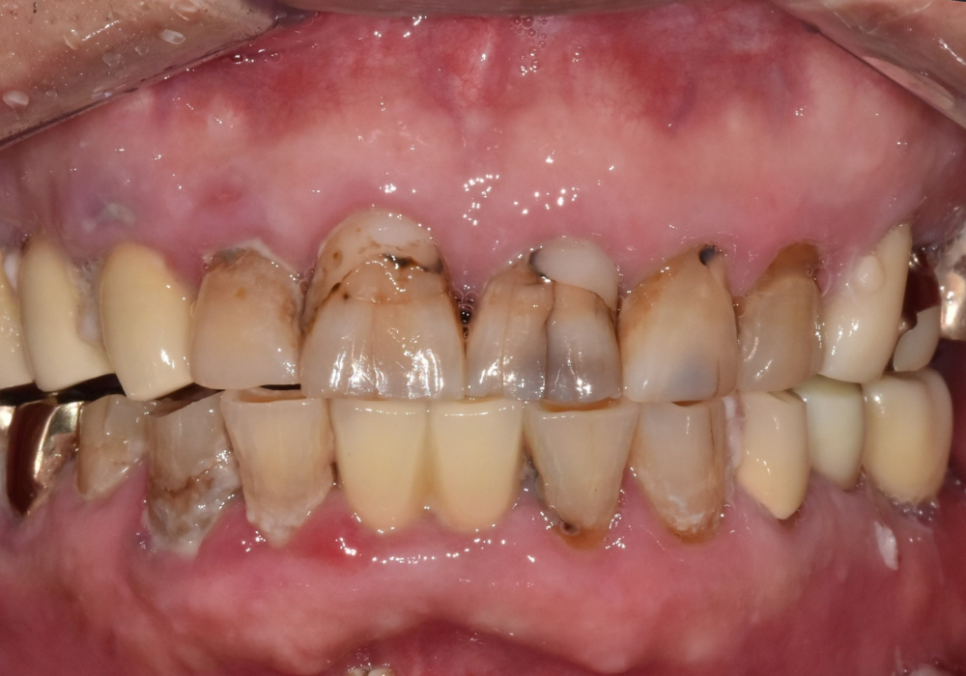

최근 내원하신 환자분은

앞니 사이 음식물 끼임이 심해지면서

치아가 검게 변색된 상태였어요.

육안으로도 깊은 충치가 보였고,

과거에 레진으로 치료했던 부위 안쪽으로

2차 충치가 진행되고 있었죠.

위의 앞니에 금도 가있네요.